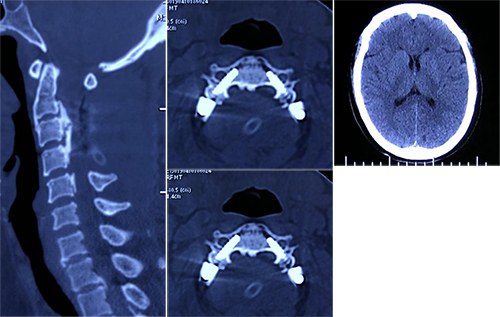

王大川主任医师团队立刻成立应急小组,并协调院内相关科室多科急会诊。谭炳毅副主任医师一边安抚患者及家属,一边仔细查体,不放过一丝蛛丝马迹。会诊医师建议行颅脑、颈部CT检查,在与CT室协调好后临时为患者开通绿色通道,第一时间行颅脑及颈部CT检查,但结果无异常发现。

患者发病急,症状重,谭炳毅副主任医师根据多年工作经验,建议行颅脑、颈部MR检查,一时间明确诊断的希望寄托到磁共振上。磁共振诊断显示,其颈部切口内血肿压迫了脊髓,造成了四肢软瘫。